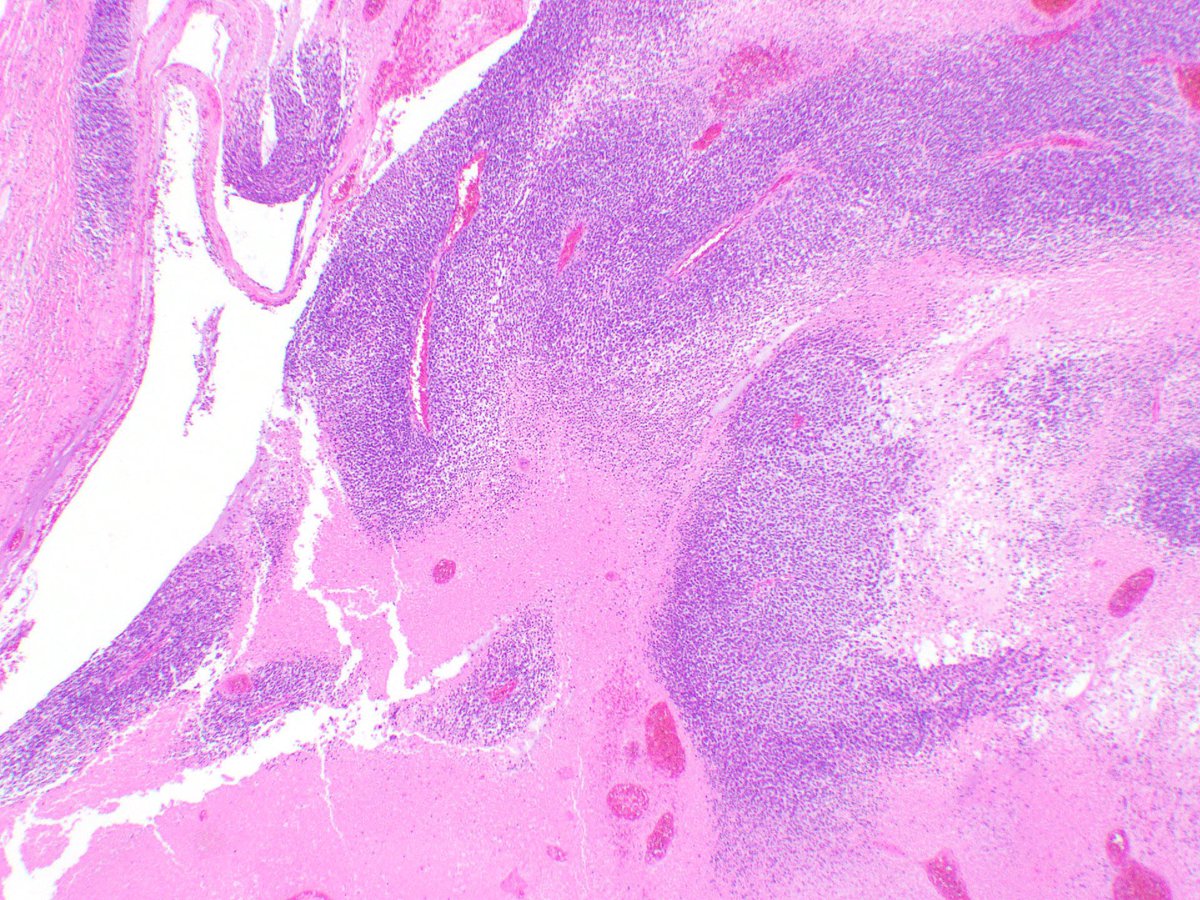

75 y/old, retroperitoneal lesion,H&E,would you like to propose any IHC to support the final diagnosis? Fiona Maclean A. Cristina Vargas Tristan Rutland MBBS FRCPA IFCAP Carlos Monteagudo Cleo Romagosa IMPERAS Henry YANG Sumanta Das @kells108 Anatomía Patológica, Hospital La Fe AP Hospital 12 de Octubre VallHebronPath